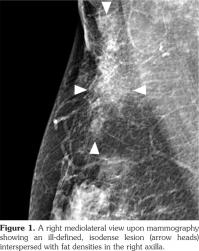

Full-field digital mammography was performed (MAMMOMAT Inspiration; Siemens AG, Munich, Germany). A right mediolateral oblique view revealed an asymmetric density in the right axilla (Figure 1). Ultrasonography was performed with a 5- to 12-MHz linear transducer (iU22; Philips Medical Systems, Bothell, WA, USA), which identified a poorly defined, elongated, homogeneously hyperechoic lesion in the subcutaneous fat layer of the right axilla (Figure 2). The lesion did not exhibit increased vascularity, except for a normal traversing venous structure (Figure 2). The lesion was surgically excised. Pathological examination confirmed the diagnosis as lipogranuloma (Figure 3). On the other hand, complete blood test results were normal.

In the breast, lipogranulomas have been reported after the release of the silicone gel from breast implants, after the application of a traumatic treatment called “Bu-Hwang,” and after phenothiazine therapy.(8,9) The mammographic features of lipogranuloma have been described in only two cases. These cases presented a bizarre-shaped lesion with bright density which proved to be lipogranuloma with osseous metaplasia and an irregular mass containing several microcalcifications.(8,10) The ultrasonographic features of breast lipogranuloma have been described in only one case, which presented an ill-defined hyperechoic lesion.(10)

Besides the breast and axilla, the ultrasonographic features of lipogranuloma have been described in the penis and scrotum, and have included cases with an ill-defined area of increased echogenicity in the subcutaneous tissue of the penile shaft,(11) a poorly defined extratesticular echogenic mass with an elongated appearance on a longitudinal scan,1 and an intratesticular heterogeneously hypoechoic mass.(12)